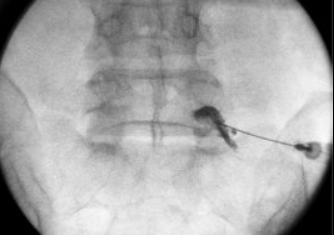

척수 조영술: 필요에 따라 시행, 척추관 내 조영제가 좁아진 모습 등 협착 소견 확인.